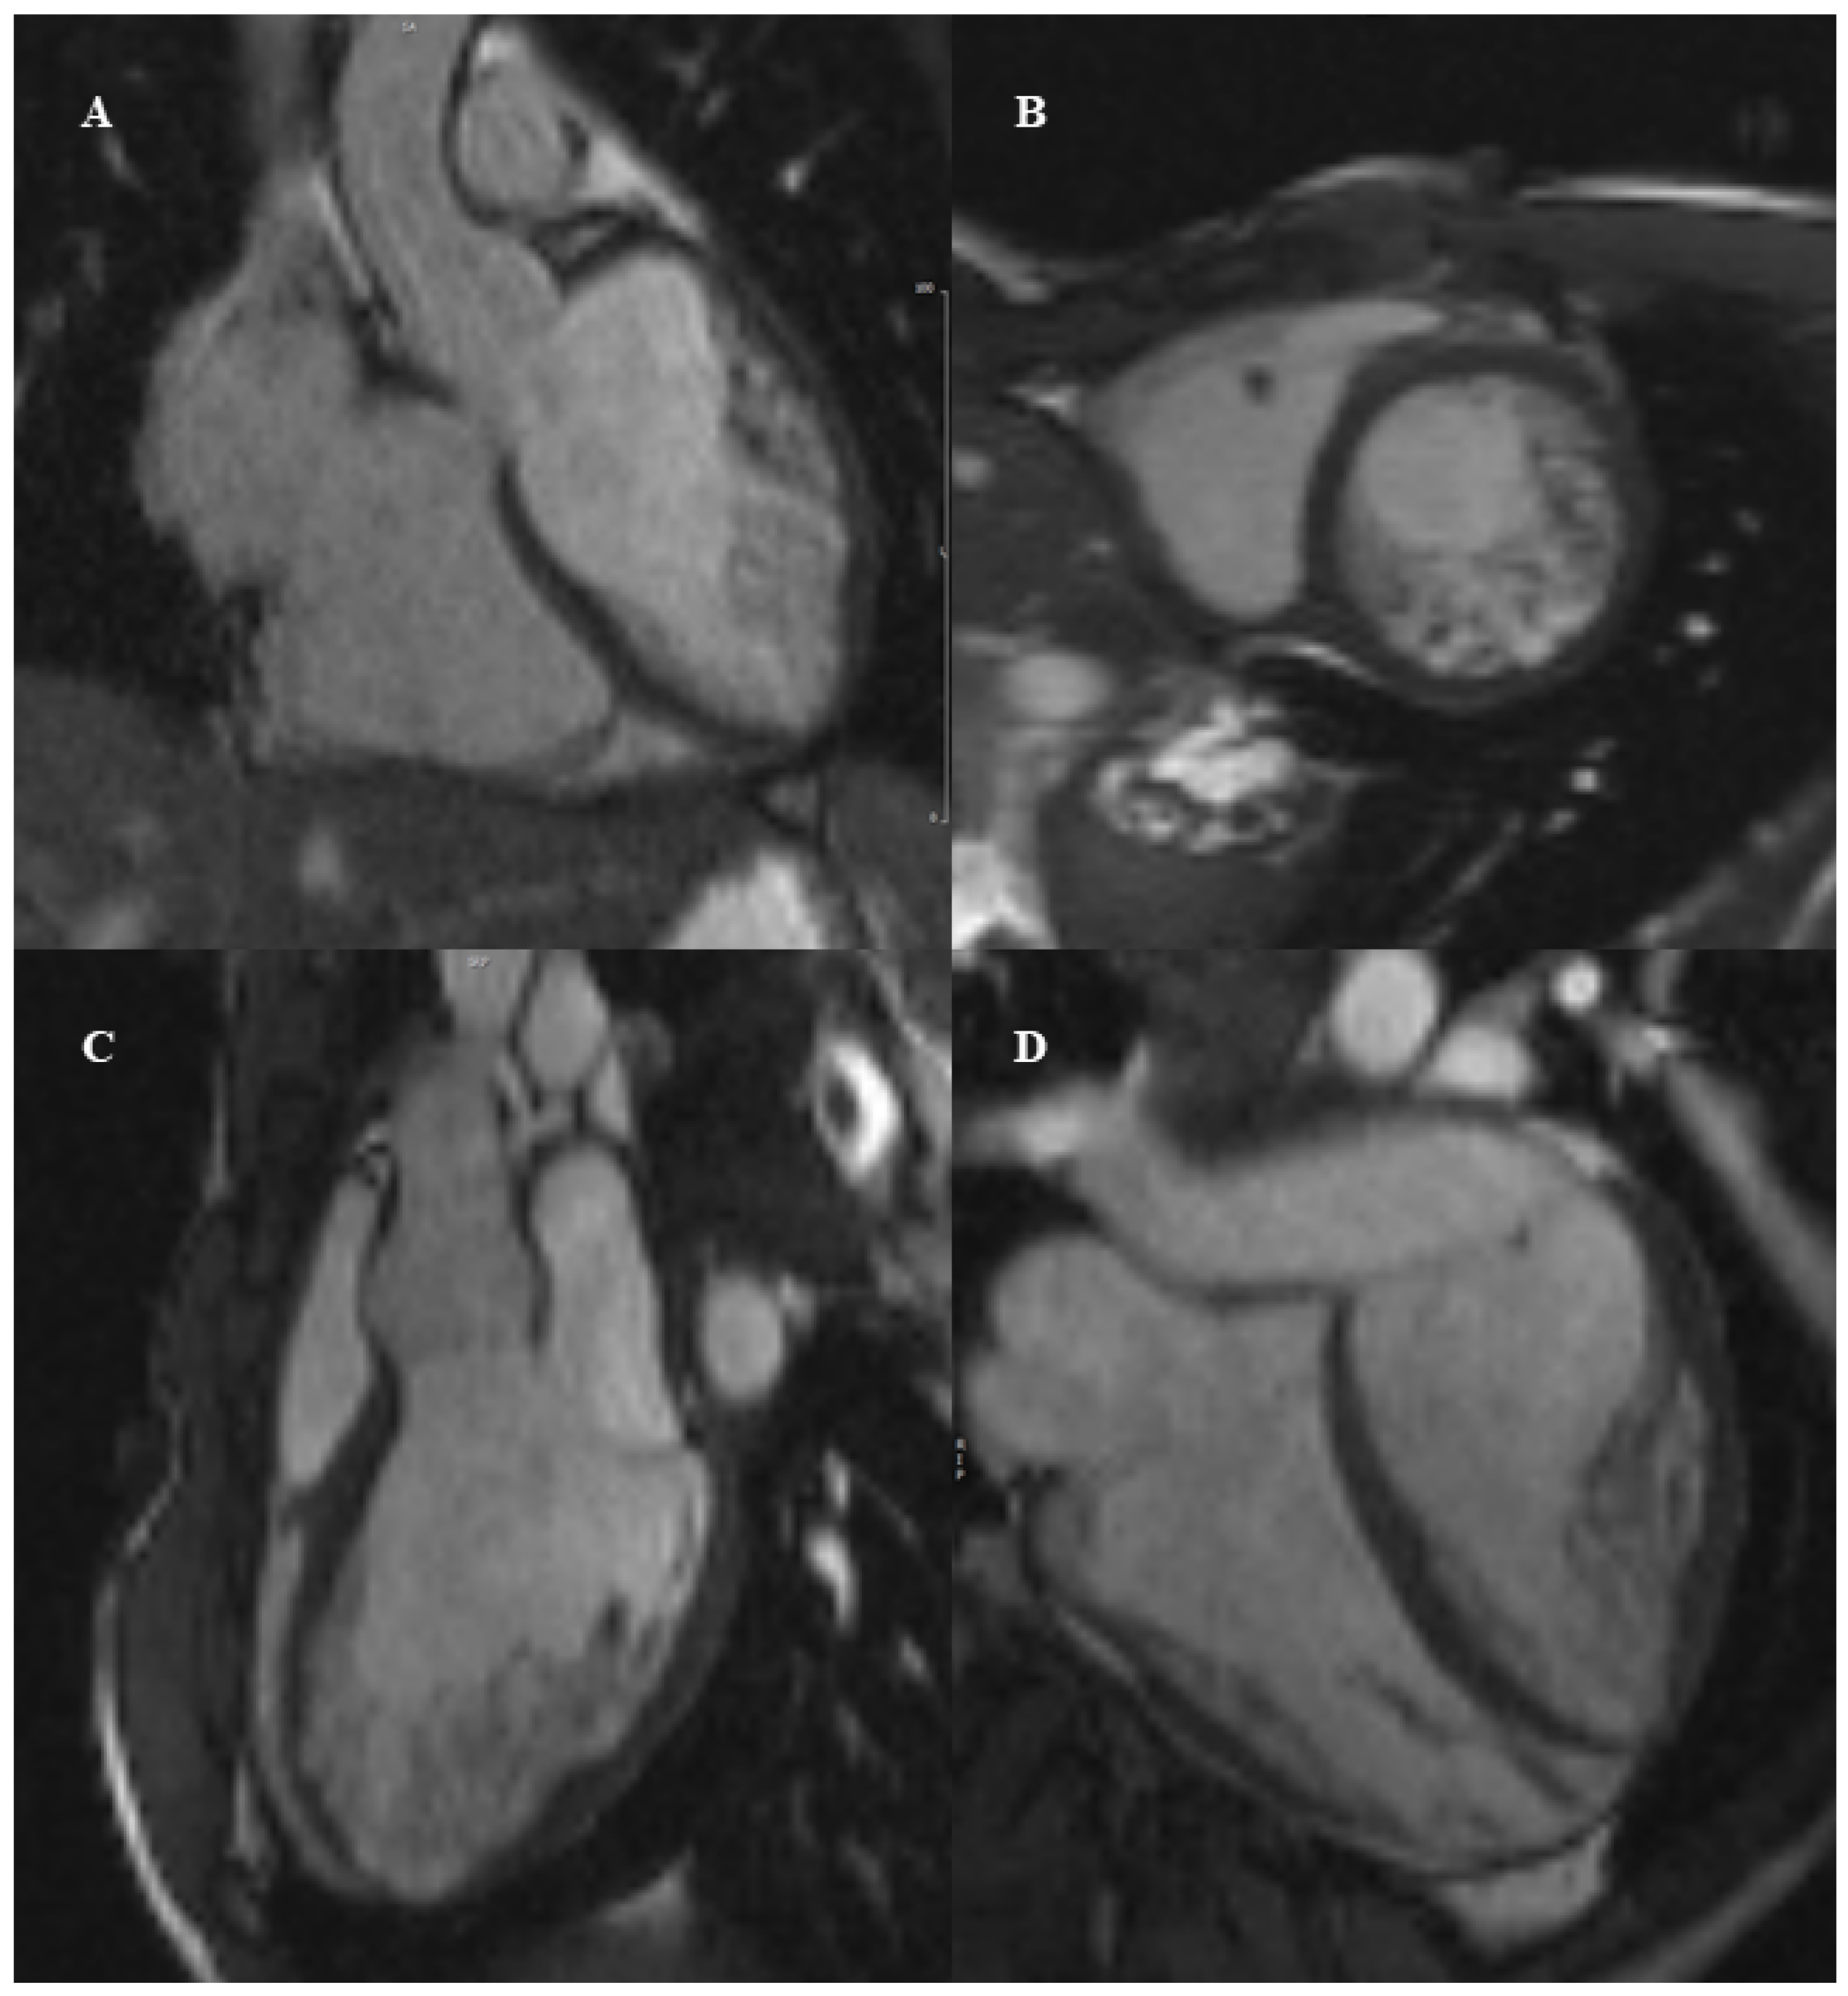

5. Left Ventricular Non-Compaction

CMR Diagnostic and Prognostic Role in Pediatric HCM